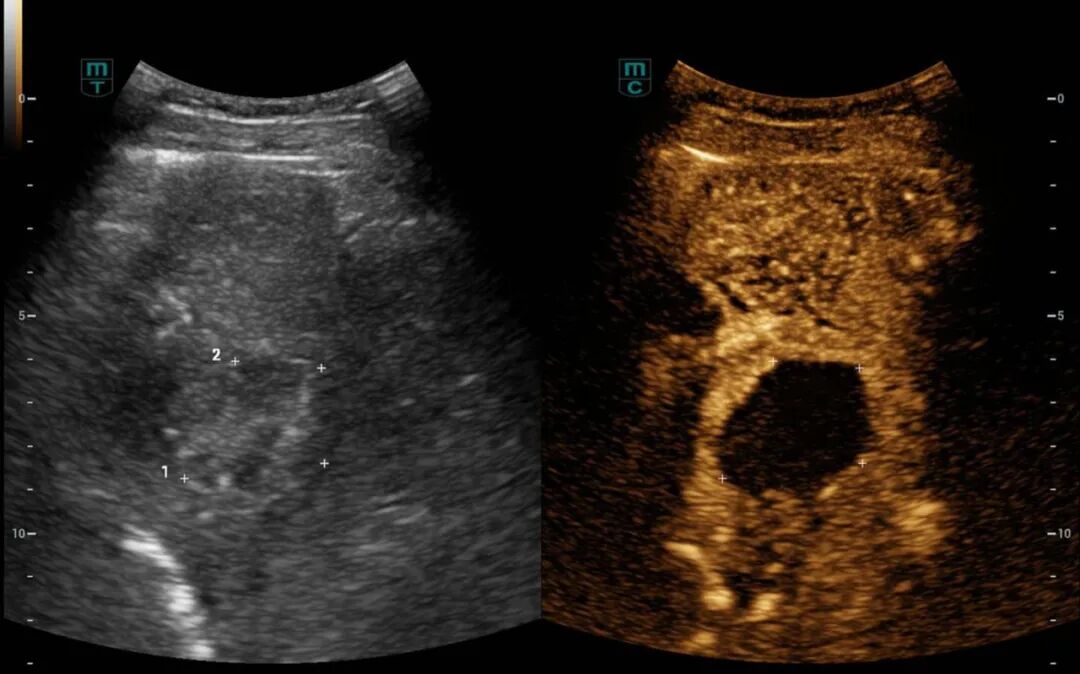

消融完成后,术者退出电极针,经超声造影评估所有消融部位达到安全范围后手术顺利结束,术后给予对症支持治疗,患者恢复良好。术后3天超声造影显示肿瘤部位呈无血供现象,周边血管结构保存完整,消融效果良好且安全。术后1月超声造影显示病灶明显缩小,消融效果显著。

▲ 术后3天超声造影